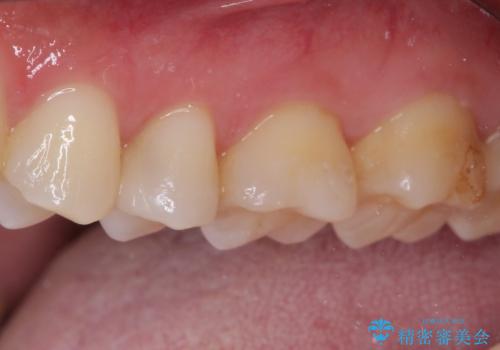

そして次の来院時、セラミックインレーを装着し、噛み合わせなどの調整を行います。

自然な色調で大変満足されました。